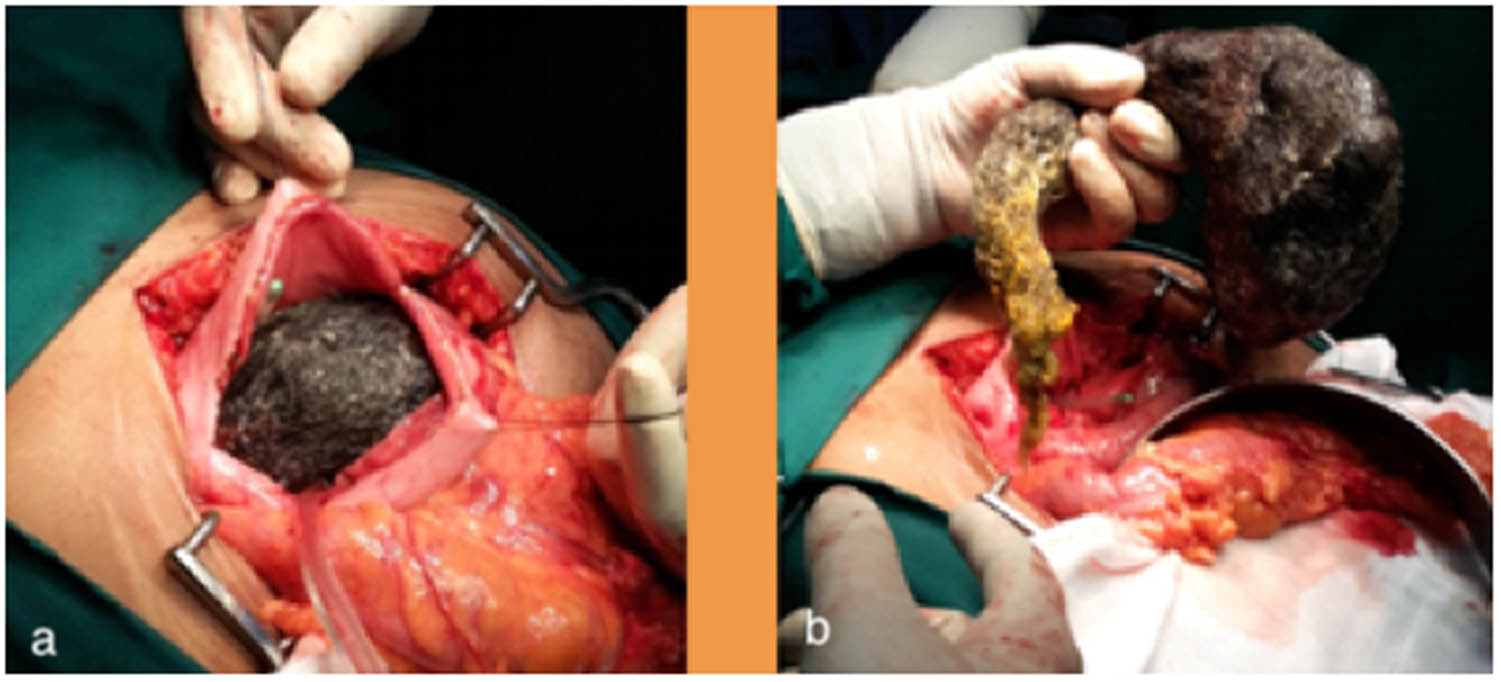

Given the large size of the trichobezoar and the presence of cholangitis and pancreatitis, the patient was scheduled for surgery. The abdomen was entered by a midline incision. The anterior gastrotomy was done between stay sutures which revealed a large, entangled mass of hair in the stomach with the tail extending to the second part of the duodenum (Figure 2). The tail of the trichobezoar was found to be obstructing the Ampulla of Vater, which confirmed the diagnosis of Rapunzel syndrome with complications of acute cholangitis and pancreatitis (Table 1). The trichobezoar was removed in-toto without peritoneal contamination (Figure 3). She had an uneventful postoperative recovery and was discharged after detailed psychiatric counselling. She was also advised regular follow-up, and three years later, the patient reports no complications. At the three years of follow-up (2019), informed consent was obtained from the patient for this study.

Panels (a and b) showing anterior gastrotomy and removal of the large trichobezoar extending from the stomach to the second part of duodenum

Specimen showing the removed trichobezoar casted in the shape of the stomach and the duodenum.